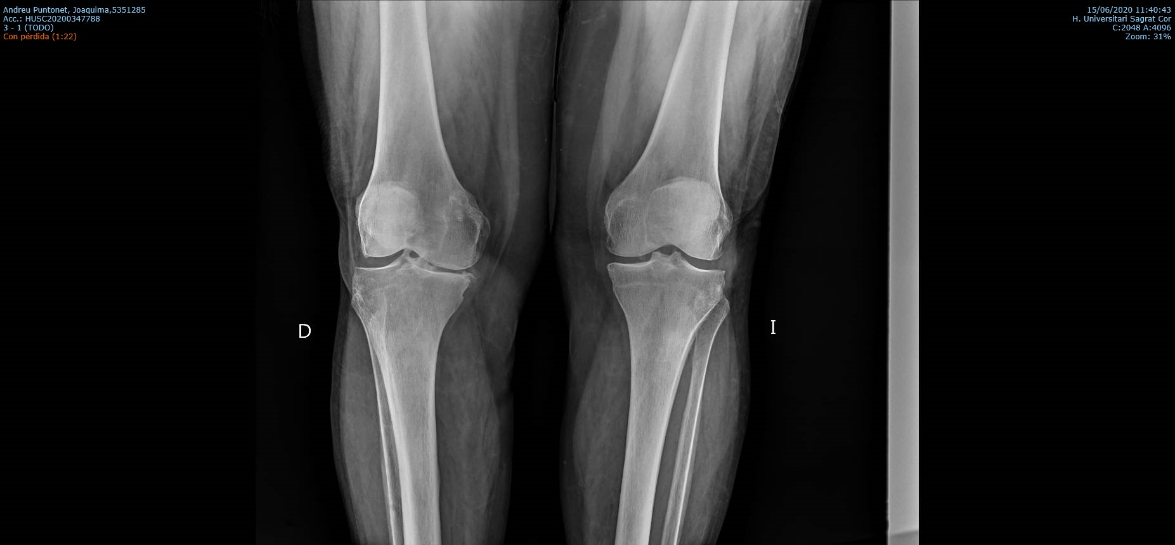

Los estudios previos para el diagnostico de una artrosis de rodilla son principalmente un examen clínico del médico y las radiografías. El examen medico habitualmente confirma dolor en la parte medial, anterior y lateral de rodilla, rigidez con reducción en el rango de movimiento, crepitación o roce con el movimiento de la rodilla y cojera durante la marcha. En la radiografía típicamente se observa los cambios en la forma del hueso y cartílago como la pérdida de grosor, deformación y endurecimiento. Ocasionalmente para confirmar el diagnóstico de la patología de un compartimiento o de una fase muy inicial, se puede usar otras pruebas de imagen como la resonancia magnética, tomografía computarizada (TC) o gammagrafía ósea que valora mejor las partes blandas alrededor de la articulación.